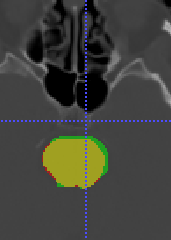

In Chapter 6, we propose an end-to-end, atlas-free 3D convolutional deep learning framework for fast and fully automated whole-volume HaN anatomy segmentation [115]. Our deep learning model, called AnatomyNet, segments OARs from head and neck CT images in an end-to-end fashion, receiving whole-volume HaN CT images as input and generating masks of all OARs of interest in one shot. AnatomyNet is built upon the popular 3D U-net architecture, but extends it in three important ways: 1) a new encoding scheme to allow auto-segmentation on whole-volume CT images instead of local patches or subsets of slices, 2) incorporating 3D squeeze-and-excitation residual blocks in encoding layers for better feature representation, and 3) a new loss function combining Dice scores and focal loss to facilitate the training of the neural model. These features are designed to address two main challenges in deep-learning-based HaN segmentation: a) segmenting small anatomies (i.e., optic chiasm and optic nerves) occupying only a few slices, and b) training with inconsistent data annotations with missing ground truth for some anatomical structures. We collect 261 HaN CT images to train AnatomyNet, and use MICCAI Head and Neck Auto Segmentation Challenge 2015 as a benchmark dataset to evaluate the performance of AnatomyNet. The objective is to segment nine anatomies: brain stem, chiasm, mandible, optic nerve left, optic nerve right, parotid gland left, parotid gland right, submandibular gland left, and submandibular gland right. Compared to previous state-of-the-art results from the MICCAI 2015 competition, AnatomyNet increases Dice similarity coefficient by 3.3% on average. AnatomyNet takes about 0.12 seconds to fully segment a head and neck CT image of dimension , significantly faster than previous methods. In addition, the model is able to process whole-volume CT images and delineate all OARs in one pass, requiring little pre- or post-processing. We demonstrate that our proposed model can improve segmentation accuracy and simplify the auto-segmentation pipeline. These contributions are released as an open-source software package called AnatomyNet, which is publicly available555https://github.com/wentaozhu/AnatomyNet-for-anatomical-segmentation. Portions of this chapter were published as part of [115].

- [121] W. Zhu and X. Xie. Adversarial deep structural networks for mammographic mass segmentation. arXiv:1612.05970, 2016.